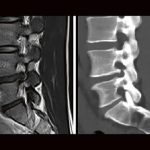

NEURORADIOLOGY DIAGNOSTIC CHALLENGE

Professor Dr. med. Ahmed Othman

Schwierige Fälle lösen und daraus lernen – Das ist der Reiz der Radiologie!

In der Neuroradiology Diagnostic Challenge lösen wir gemeinsam spannende und besonders lehrreiche Fälle aus der Neuroradiologie. Ziel: Mit jedem Fall ein wenig besser werden und dabei Spaß haben!